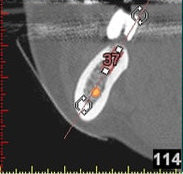

In komplexen Fällen, z. B. der Implantatversorgung eines kompletten Kiefers, oder bei schwierigen Knochensituationen bietet die 3-dimensionale Computerdiagnostik bzw. Planung und Durchführung erhebliche Vorteile und Sicherheit für den Patienten (siehe Bild 1 und 2).

Auf Basis einer computertomografischen (CT-) Kieferaufnahme ist eine dreidimensionale Darstellung der Knochen möglich. Der Zahnarzt kann dann am Computerbildschirm die Knochenqualität (z. B. Knochendichte) beurteilen und die optimale Position der Implantate im Vorfeld planen. Durch Verwendung spezieller Röntgenschablonen lässt sich auch die erwünschte Zahnstellung in die Planung einbeziehen. Die Simulation der OP erlaubt, das zu erwartende Ergebnis mit größtmöglicher Sicherheit vorherzusagen und dem Patienten am Bildschirm zu veranschaulichen.

(siehe Bild 3 und 4).